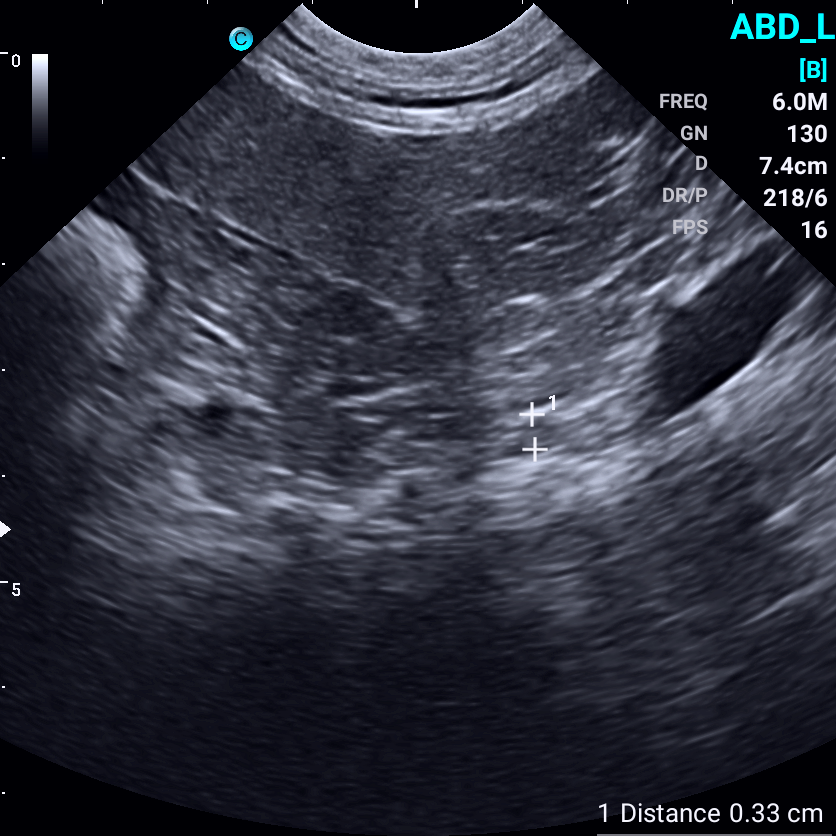

Images from the Sonoeye P6